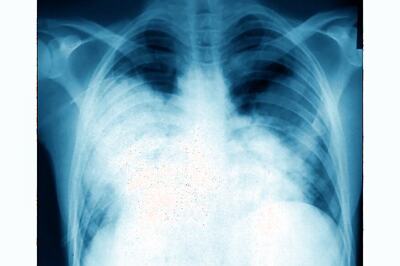

Signs to Treatment, Everything You Need to Know About Lung Cancer

In India, about 70,000 new cases of lung cancer are diagnosed every year with almost 70% of them detected at an advanced stage.